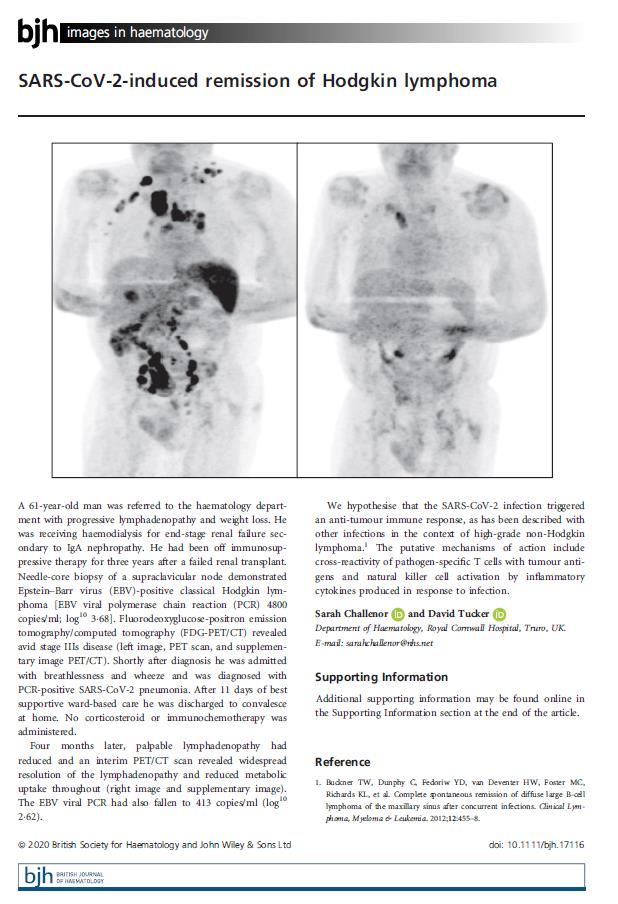

他因为肾病,接受过肾移植,但是失败了,现在正在接受血液透析治疗。然后,因为发现淋巴结肿大到血液科就诊,做了淋巴结穿刺和PET-CT检查(可以比较灵敏、准确、特异及精确定位的检查方法,很贵),确诊为经典霍奇金淋巴瘤(就是淋巴系统的肿瘤,可能和他感染有EBV病毒有关),这名男子在确诊淋巴瘤后不久,还没开始治疗,就因为呼吸困难诊断为新冠肺炎,住院进行了11天的新冠的支持治疗,治疗后就回家休养生息。

时间又过去了四个月,这名男子发现身上的淋巴结肿大程度减轻了(期间没有接受针对淋巴瘤的治疗),又做了PET-CT确实发现淋巴结瘤情况有了好转,身体感染的EBV病毒量也有了下降。